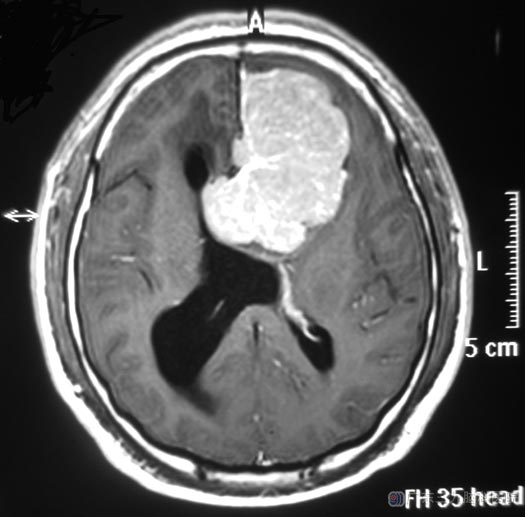

这天早晨八点左右,家人发现他进了卫生间后好久都没有出来,撬开门,发现高先生晕厥在里面。“120”急送当地医院,当时他双侧面部潮红,小便失禁,约一小时后神志清醒,不能回忆,没有不适感觉。头颅CT检查提示:左侧前颅窝占位;广东三九脑科医院头颅MR检查提示左侧额部镰旁占位,大小约54.5mm×68.6mm×55.1mm,邻近双侧侧脑室、胼胝体及脑组织明显受压,综合神经外科 鲁明主任初步考虑为脑膜瘤。

完善术前准备后,鲁明主任主刀,在全麻下行左侧额部大脑镰旁脑膜瘤切除术,显微镜下见肿瘤呈肉红色,质软,血供丰富,边界清楚,完整切除肿瘤,嗅神经、双侧大脑前及骈周动脉保留完好。术后高先生很快康复。病理结果为:过渡型脑膜瘤(WHO I级)。